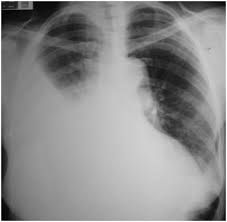

Hemotórax.

Es una

acumulación de sangre en el espacio existente entre la pared torácica y el

pulmón (la cavidad pleural).

El médico

puede notar disminución o ausencia de los ruidos respiratorios en el lado

afectado. Los signos de hemotórax se pueden observar en los siguientes

exámenes:

. Radiografía de tórax